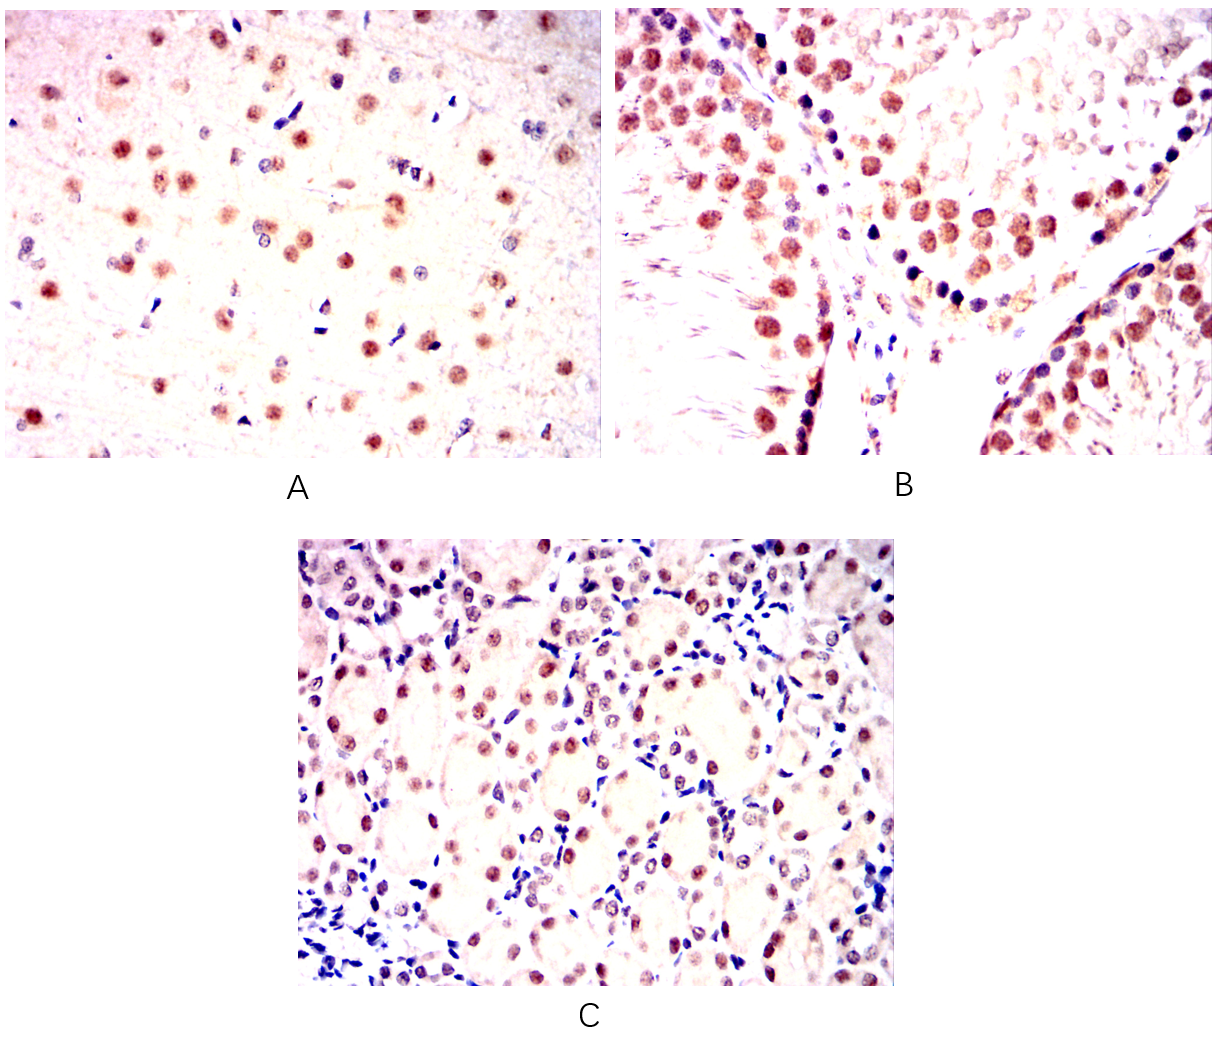

分类: 科研抗体货号: 20345别名: Isl-1; ISLET1应用: IHC,IF反应种属: Human,Mouse,Rat,Rabbit

分类: 科研抗体货号: 20344别名: Isl-1; ISLET1应用: IHC,IF反应种属: Human,Mouse,Rat,Rabbit

分类: 科研抗体货号: 20375别名: HNF3B; TCF3B; MGC19807应用: WB,IHC反应种属: Human

分类: 科研抗体货号: 20356别名: PAK65; PAKgamma应用: WB,IHC,IF反应种属: Human,Monkey